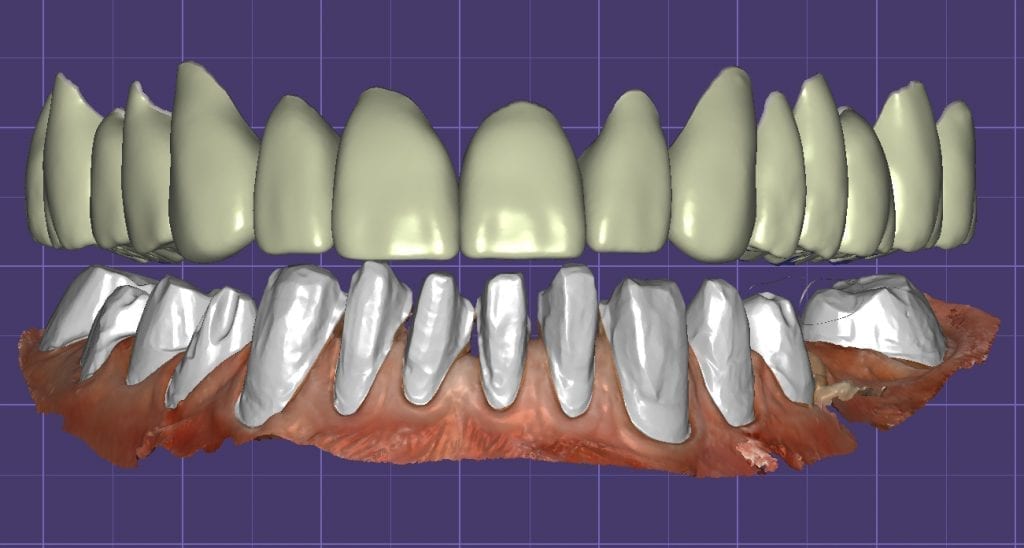

Once the appropriate library is chosen, the digital wax ups are performed. In the subsequent photos you can see the transparent overlay of the wax-ups to the original position of the existing dentition

Once the case is designed to the ideal vertical dimension then multiple shells can be fabricated for treatment. The wax up model can be uniformly reduced by .5mmm’s circumferentially and a temporary shell can be designed. Once the teeth are prepared, these shells can be relined and seated onto the preps.

Over the course of a few appointments, the vertical dimension was reduced and the temporaries were adjusted to the patient’s desires. The new upper and lower arch were captured with the Medit i500 and the jaws were related to each other.

This was then imported into exocad where the prepped arches from a few weeks prior were force matched to the new bite